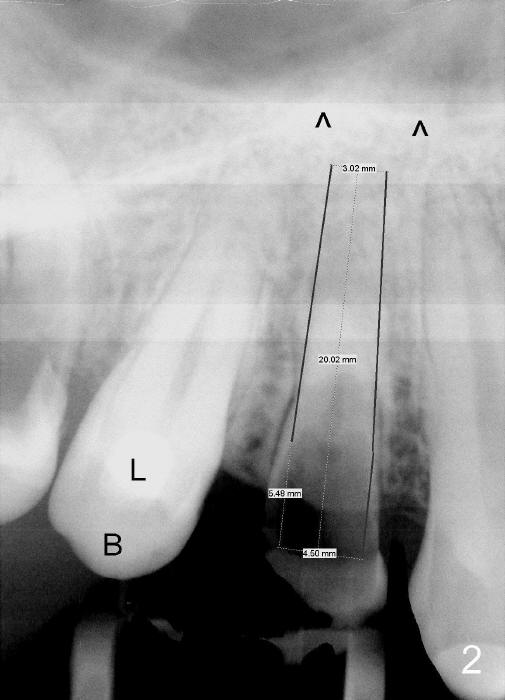

A 25-year-old black man has poor dentition. The tooth #5 is non-salvageable (Fig.1-6). Although the 1st bicuspids belong to the posterior teeth, anterior sensor holders should be used to show the sinus floor (Fig.1,2: ^). In contrast, PAs in Fig.3,6 (trimmed mesiodistally) are taken with posterior sensor holders; the sinus floor is out of view.

A long implant will be placed (possible 4.5x20 mm, Fig.2). A typical 1st bicuspid has 2 canals. In this case, there are most likely two roots (Fig.3): buccal (Fig.4 green dashed line) and lingual (Fig.5 pink dashed line).